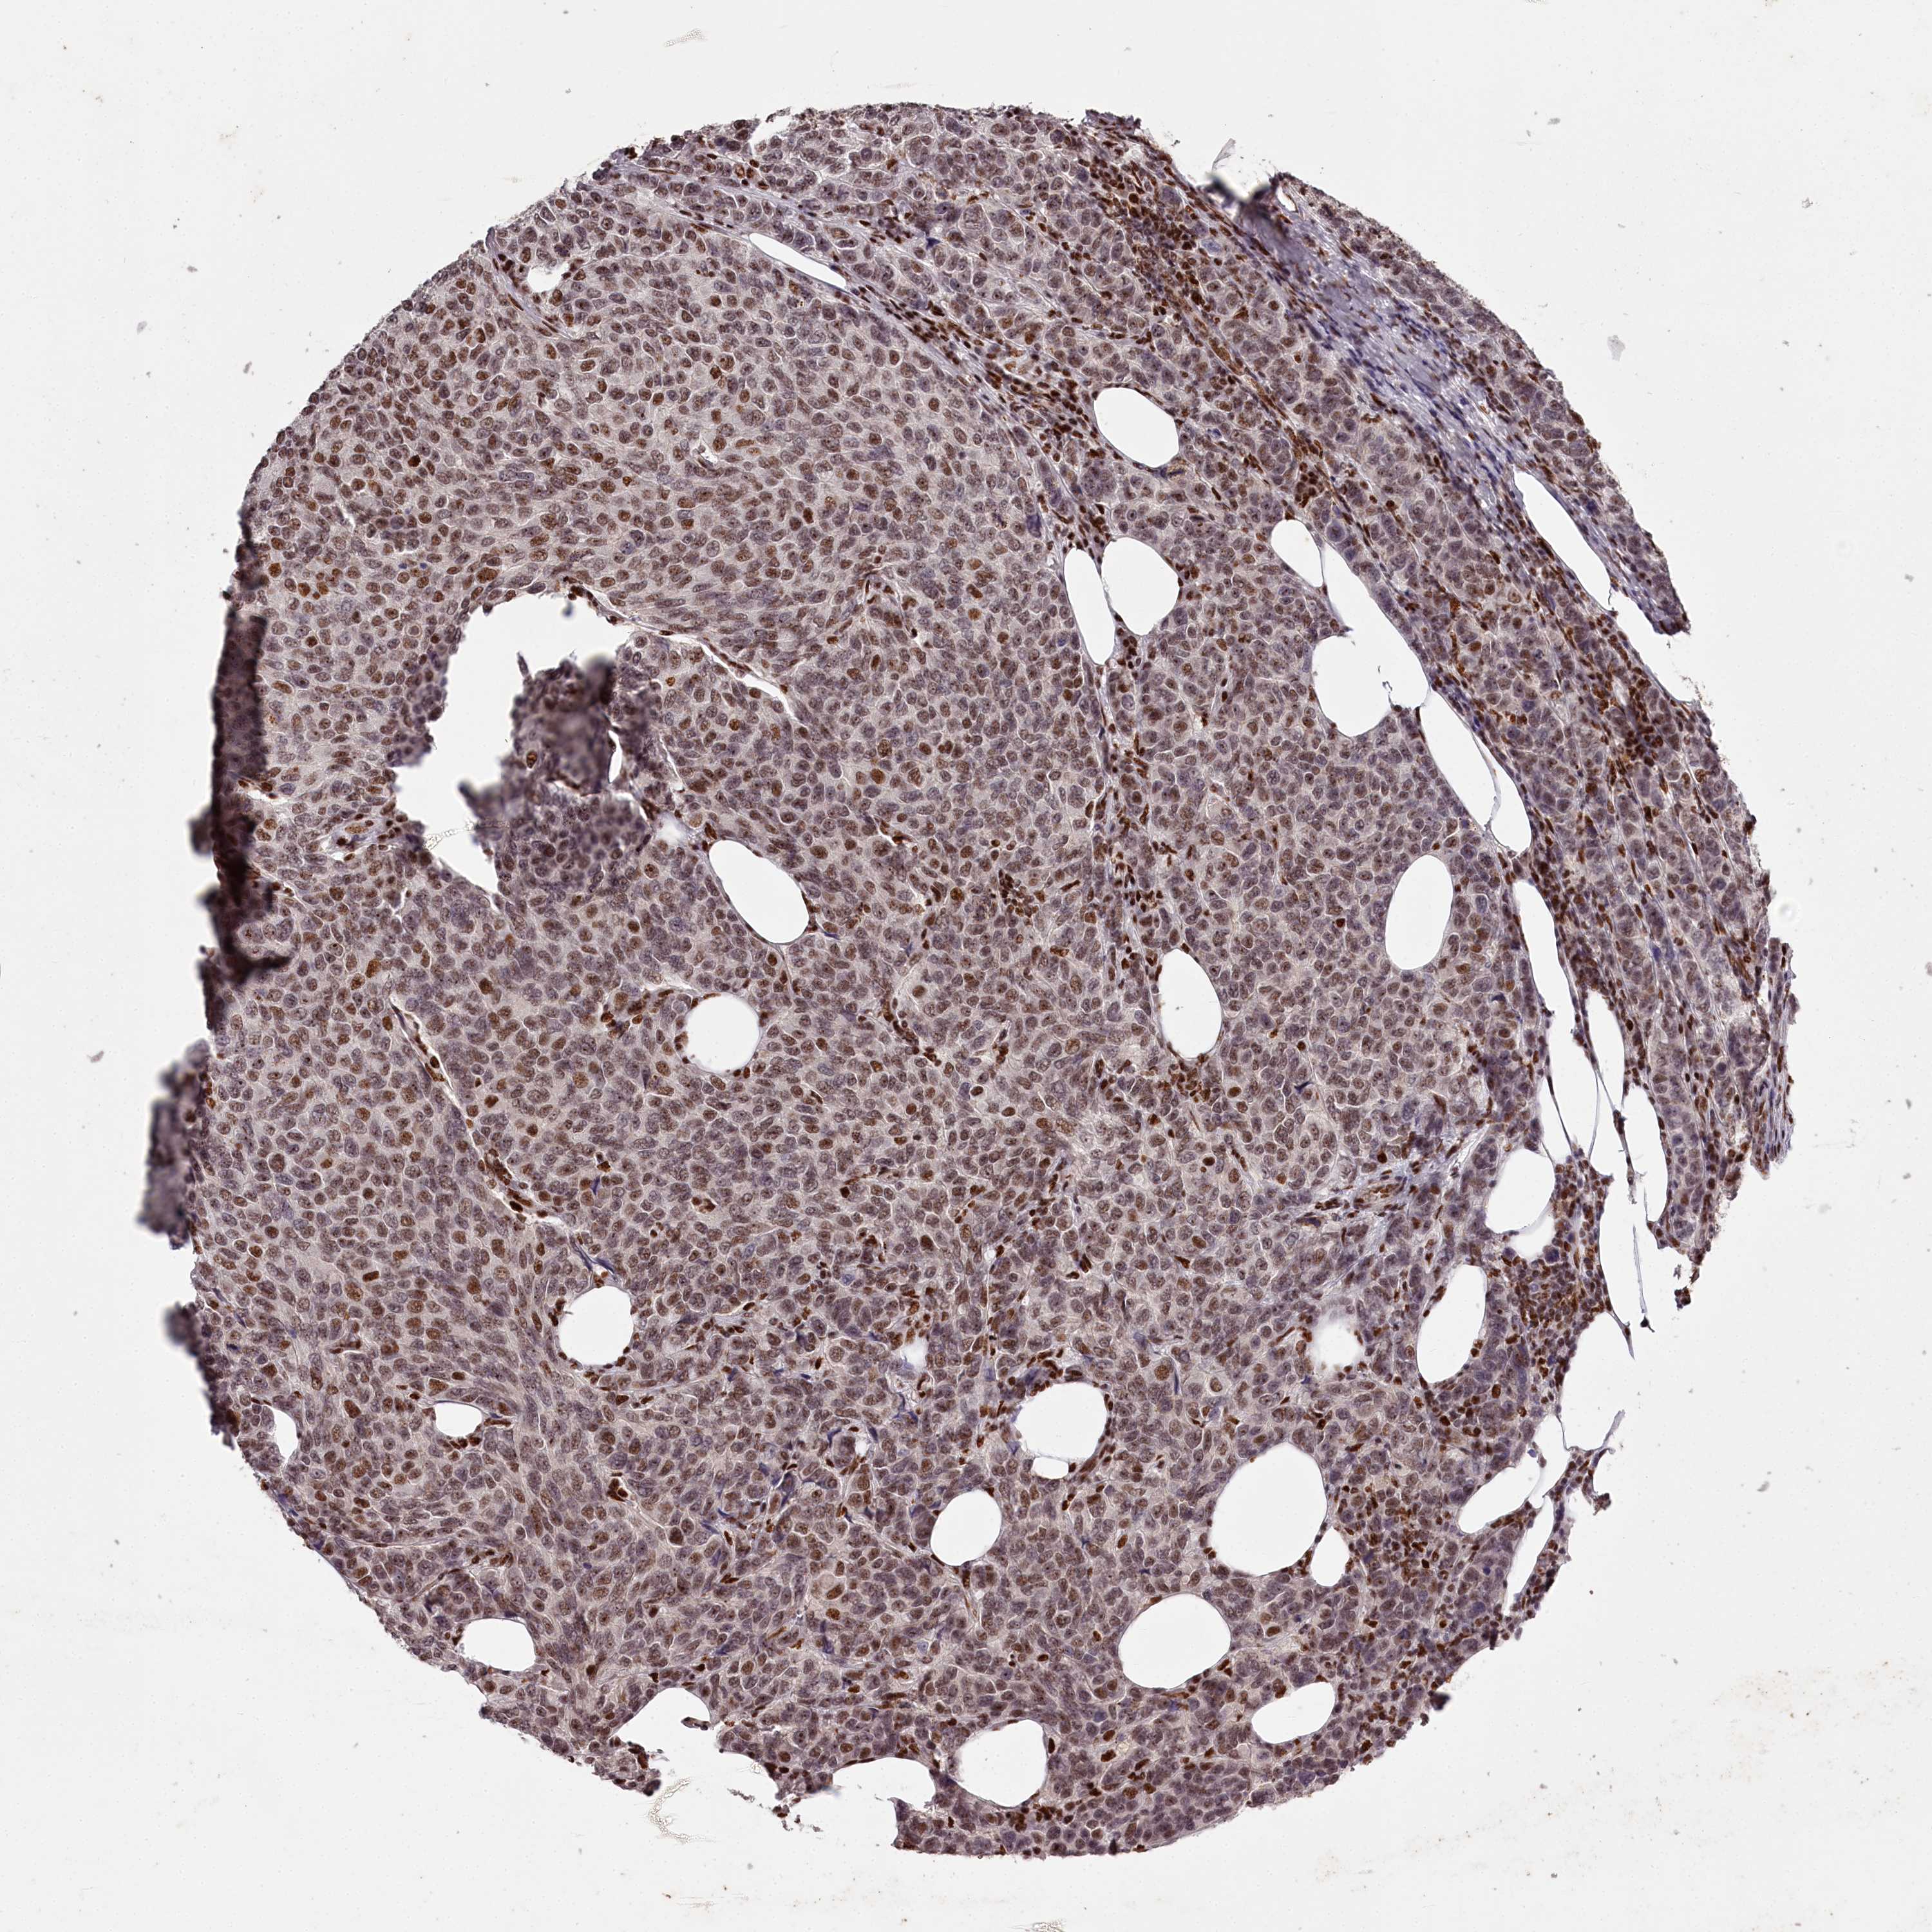

CANCER BREAST CANCER Show tissue menu

BRCA TCGA BRCA VALIDATION PROTEIN EXPRESSION